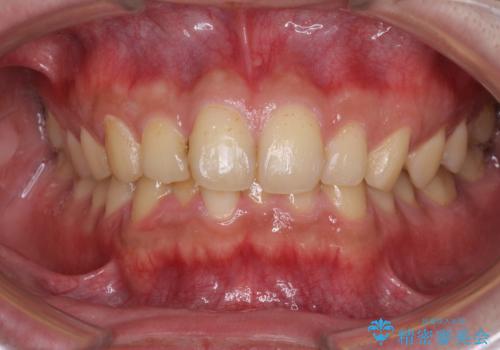

開咬とデコボコを整える インビザライン矯正治療

- 前歯の開咬と叢生を気にして来院された患者様です。

開咬の治療は、前歯を閉じるように動かすとともに、上下臼歯を圧下(骨内にめり込ませる)させることで進めて行きます。

インビザラインは臼歯の圧下を効果的に行えるため、インビザラインを用いて矯正治療を行うこととしました。また、アンカースクリューを用いて、口元の突出感の改善を図りました。

オープンバイトは舌の突出癖により誘発され、治療後も突出癖が残っている容易に後戻りしてしまいます。

治療期間を短縮するためにも、舌突出癖の改善が極めて重要となります。